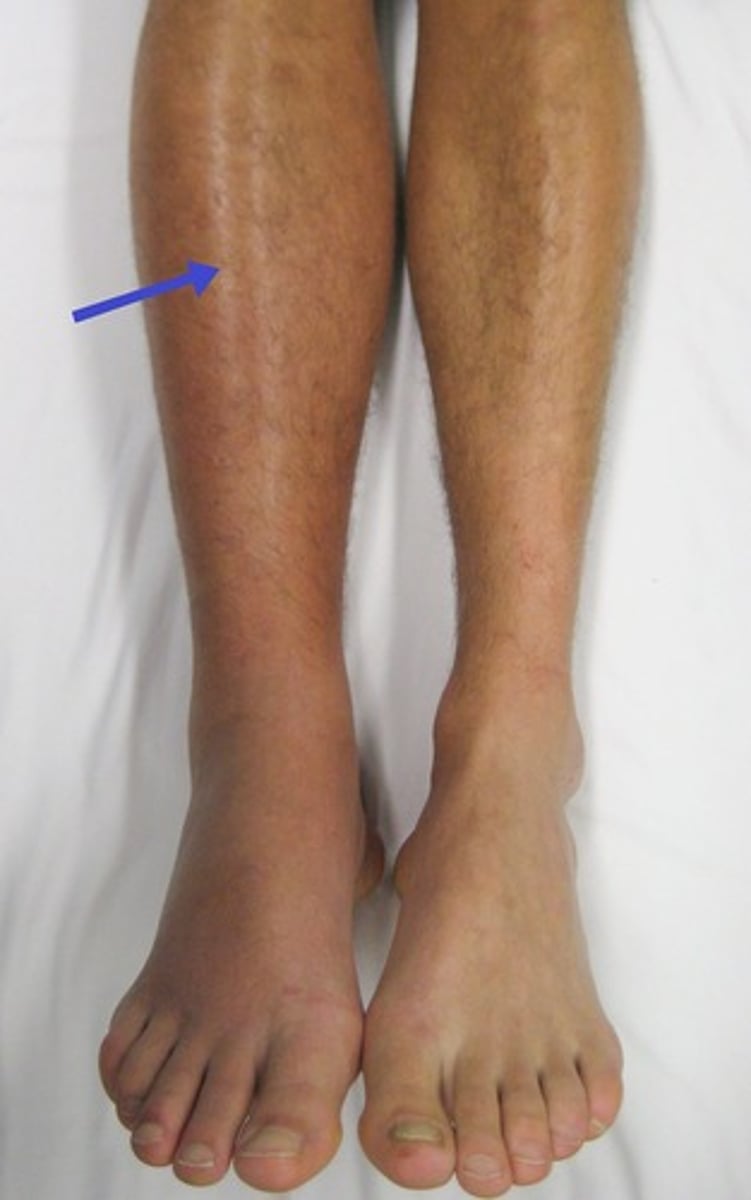

What are the DVT s&s & how to dx

- s&s: edema, erythema, pain; unilateral

What is compartment syndrome (acute)

- high pressure within a body compartment (fascia - contains muscles, nerves & vessels)

- due to injury's inflammatory sequelae causing increase in volume

- emergency! risk of total loss tissue/extremity/necrosis

What are the s&s of compartment syndrome

The "6 P's"

- worsening pain (sudden)

- pallor

- paresthesia (pins & needles, nerve supply is impacted)

- puffy (edema)

- paralysis (of distal segments)

- pulses are usually normal!!!